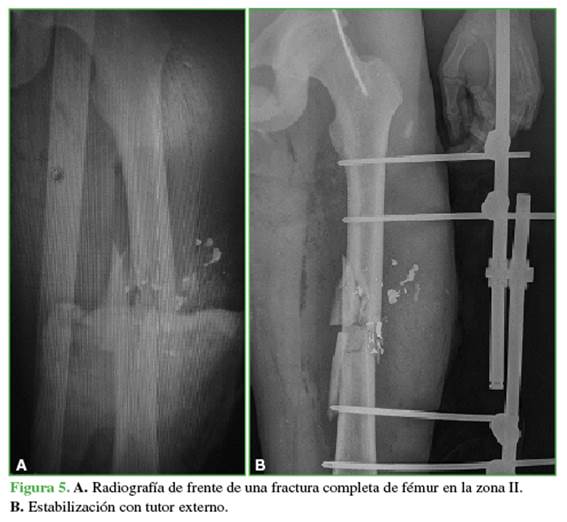

Con respecto al tratamiento inicial, los pacientes con fracturas completas (71,43%) fueron estabilizados con fijador externo (Figura 5).

Los métodos de fijación utilizados se distribuyeron de la siguiente forma: 19 (54,29%) con clavo endomedular (Figuras 6 y 7) y siete (20%) que comprometían a la zona III con placas anatómicas bloqueadas.